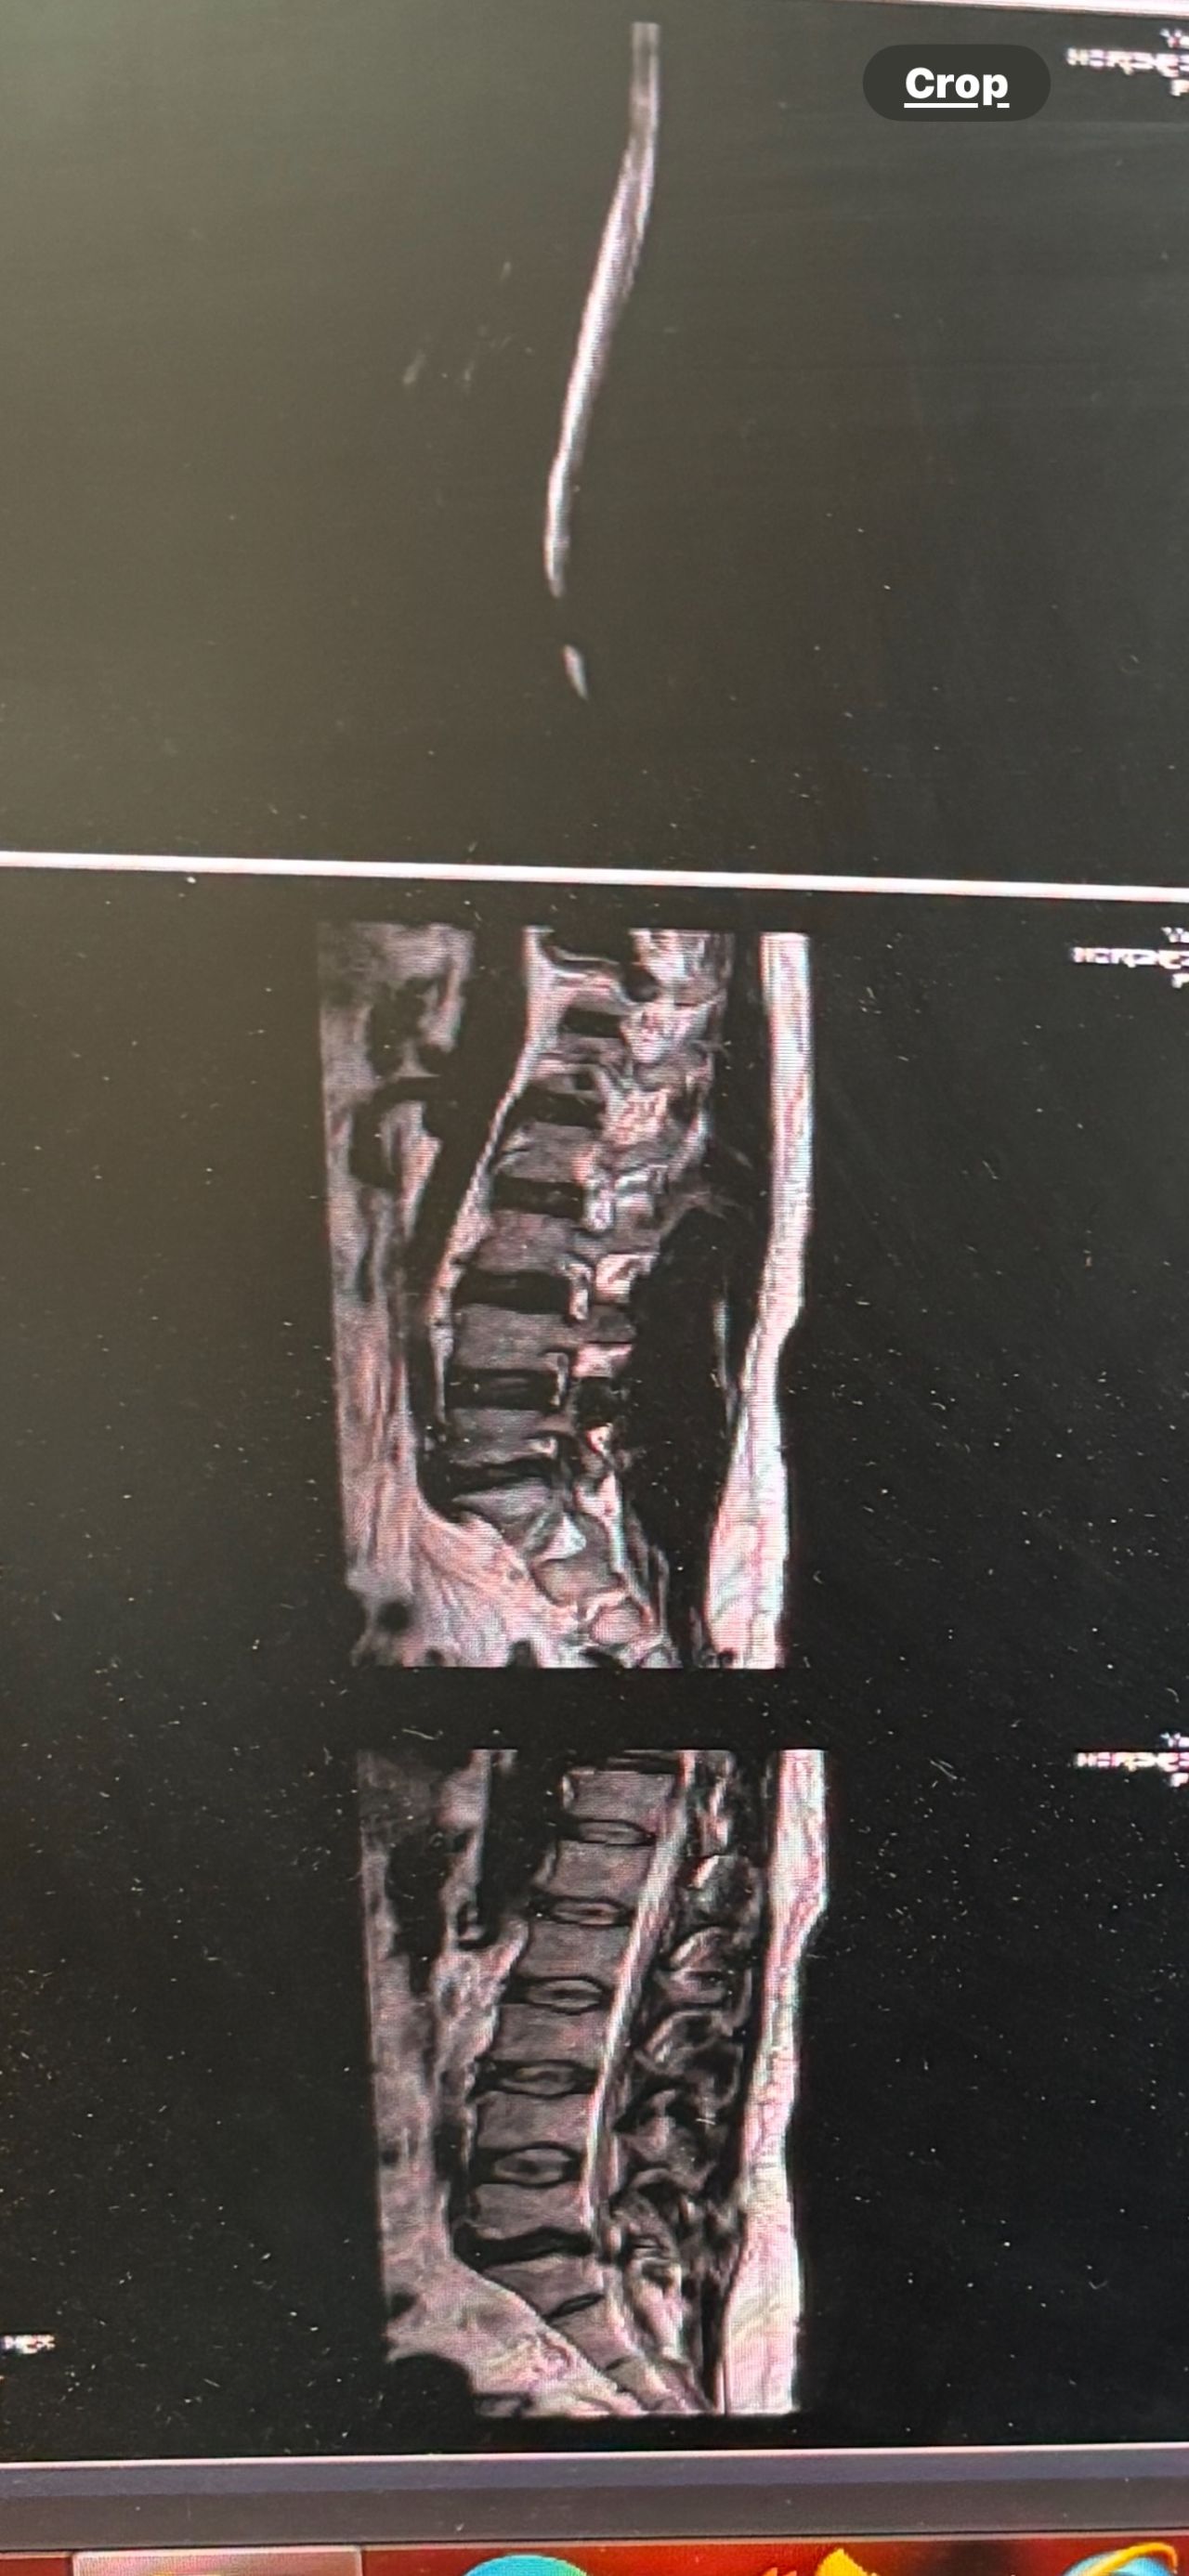

41 years old man presented to my clinic in October 2023 with acute and sever R neck pain with radicular pain to his R upper extremity along C6 dematom since 2 weeks ago. Examination didn’t show any upper motor signs. Was suggested urgent surgery

I ordered EMG/ NCV : showed mild R C6, C7 irritation without any active axonal loss

In his MRI was reported R. para R. IVF Massive extrusion. I decided to control his pain and manage this patient with reevaluation of patient every other session. For 5 sessions i just used acupuncture and laser and IFC and mild adjustments to his R. T3-T7 and mild arthosteem to above and below involved segment. Cervical adjustment considered contraindicated for this patient. From session 6th- 8th i started to use mild/gentle cervical decompression. He used soft cervical collar all the time. His pain decreased by 80 percent

I gave him cervical traction pump to be used 3-5 times per day at home for the next 3 months and i released the patient. He was evaluated every week once for one month and after that every 2 weeks. After 3 month I repeated MRI. Size of the herniated disc was reduced greater than 50 percent. Asked him to do another mri in 6 months

In general: Precise selection of the patients, examination,diagnosis, plan of management, reevaluation and treatment can be done by doctors of chiropractic for the patients with spinal disc herniation and stenosis Moreover giving reasonable time to these kind of patients under direct supervision by their chiropractic doctors can prevent unnecessary surgery. Proper selection of these kind of patients is another important fact that can be done precisely by chiropractors.

MRIs before and after proper management of this patient: